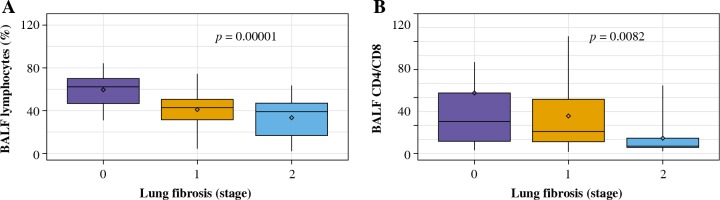

The total cell count and relative number of lymphocytes in BALF were significantly lower in patients with lung fibrosis stage 1 and stage 2 comparing to those without lung fibrosis (stage 0) (Table 4, Fig. 2A). Lymphocytosis exceeding 30% was noticed in all patients with no radiologic signs of lung fibrosis, 77% of patients with stage 1 lung fibrosis, and 68% of patients with stage 2 lung fibrosis.

Fig. 2

BALF results in relation to the presence and extent of lung fibrosis in patients with hypersensitivity pneumonitis. A) The percentage of BALF lymphocytes in the groups with no lung fibrosis (stage 0), with lung fibrosis presenting as diffuse reticulation and traction bronchiectasis (stage 1), and with lung fibrosis presenting as diffuse reticulation, traction bronchiectasis, and focal honeycombing (stage 2). B) The proportions of T lymphocytes CD4/CD8 in the groups with no lung fibrosis (stage 0), with lung fibrosis presenting as diffuse reticulation and traction bronchiectasis (stage 1), and with lung fibrosis presenting as diffuse reticulation, traction bronchiectasis, and focal honeycombing (stage 2)

CD4/CD8 index was the highest in case of patients with no signs of lung fibrosis, while the lowest index was observed in patients with advanced lung fibrosis; the differences between the three examined groups were significant (Table 4, Fig. 2B).